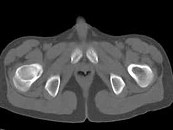

- 单项选择题男,13岁, 右髋部疼痛不适,无红肿, 结合所提供的图像,最可能的诊断是 ( )

E、骨纤维结构不良